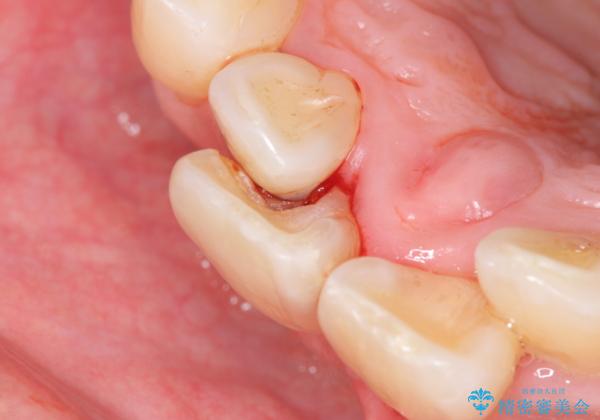

- 前歯の重なったところが虫歯になり、物理的にアプローチが難しい状態でした。

矯正治療前に虫歯を取り、歯並びが良くなってから本格的にセラミック治療を行いました。

左上1はジルコニアクラウン(スペシャル)で治しました。スペシャルの場合は写真をとり、オリジナルの色味で作成することが可能です。